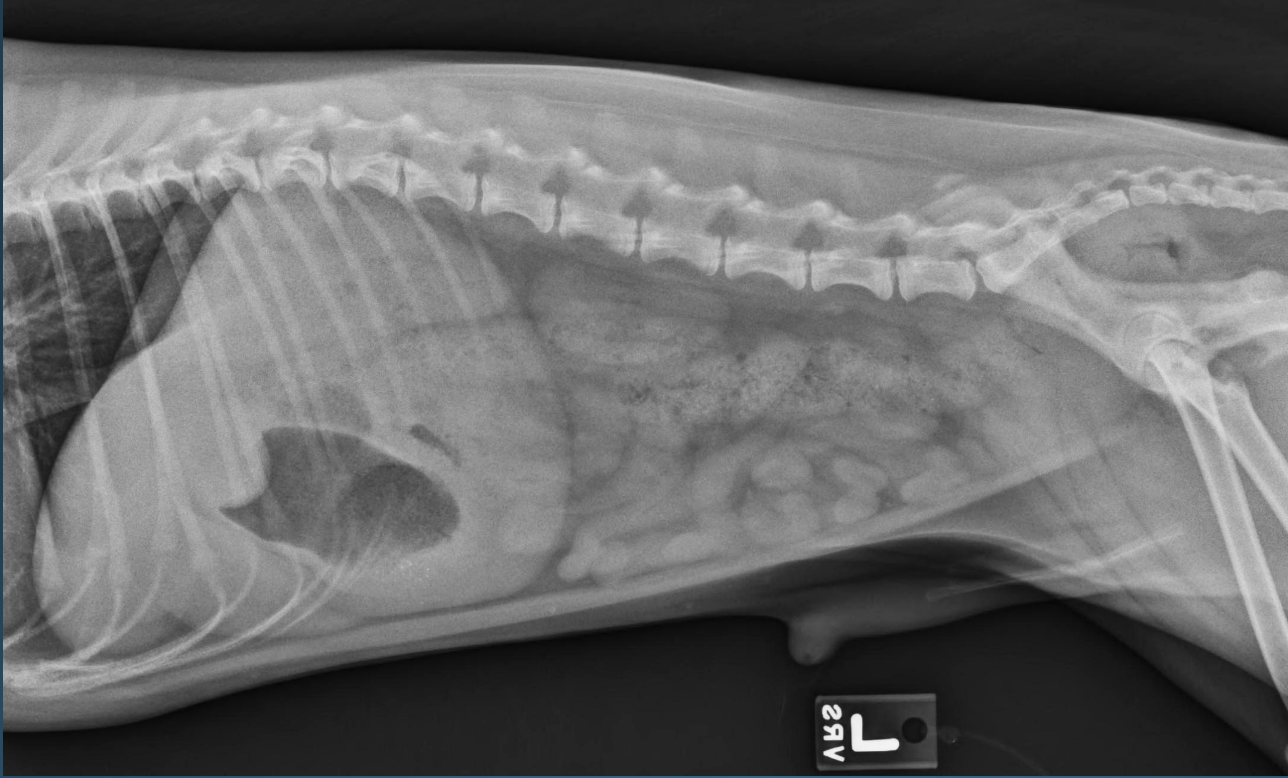

Q

What is shown in these images?

A

canine acute gastric dilation

-pylorus is still in the normal place; right and more ventral